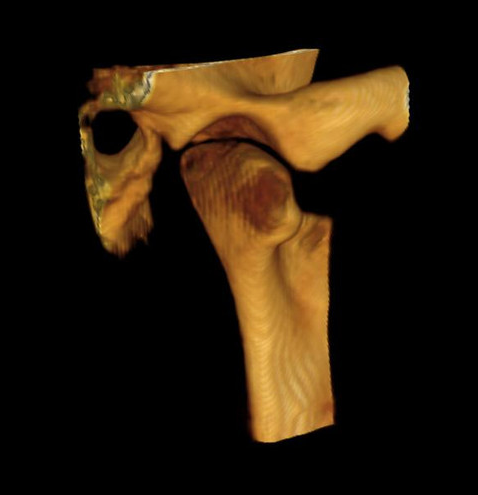

With an image resolution of up to 90 μm, the CS 9300 delivers a superb level of detail that’s ideal for a range of clinical applications, including implants, oral and maxillofacial surgery, orthodontics, and more.

Ability to collimate field of view to suit your diagnostic requirements3D options include Focused field, Single/Dual Jaw, TMJ (2x and 4x), Sinus, and Maxillofacial exams.